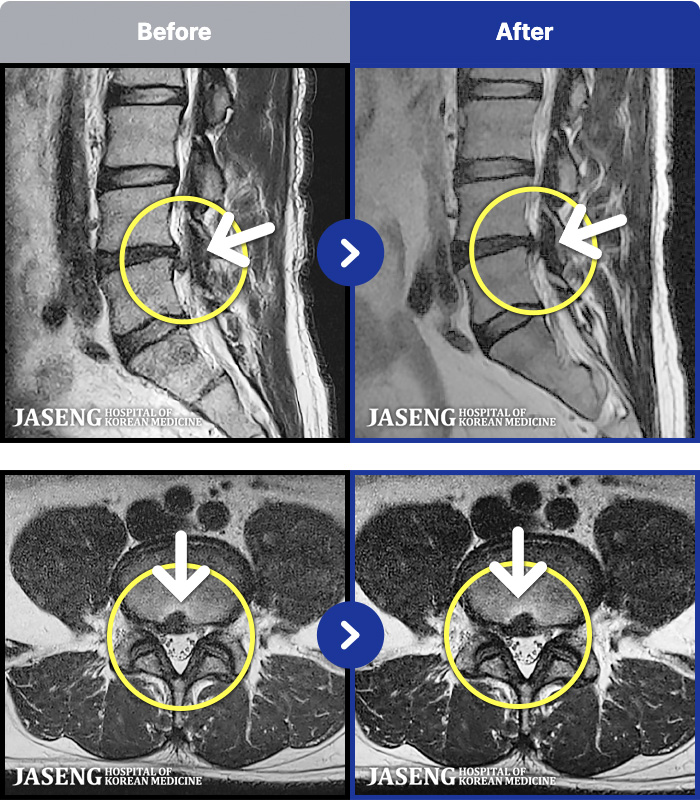

1,237 MRI ũ ʸ Ȯϼ.

㸮 ϻ .